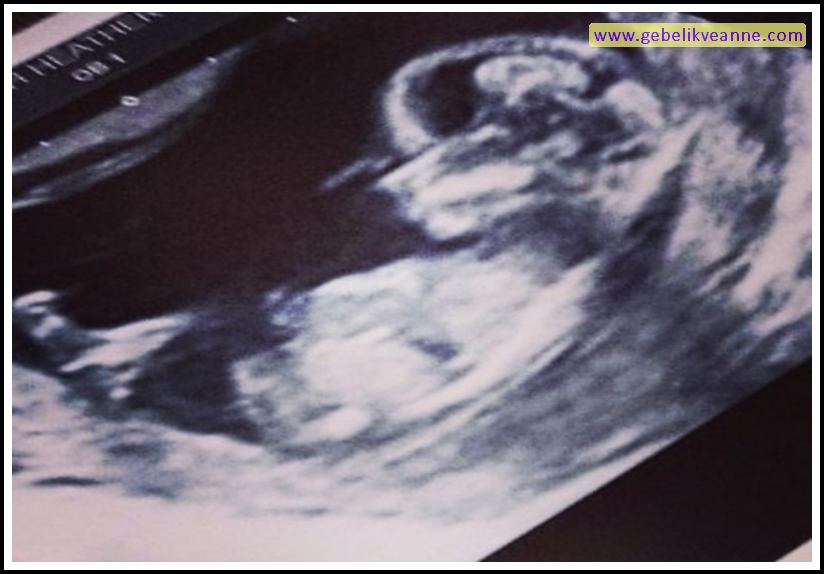

21 Haftalık Gebelik (Hamilelik) Ultrason Görüntüleri

Source: www.gebelikveanne.com

20 haftalık bebeğin 4 boyutlu ultrasın görüntüs. 2 ve 3 boyutlu ultrason görüntüsü. Bu dönemde bebeğin kalp atışları da ultrason yardımıyla anne ve baba adayı.